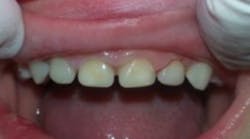

Leigh was three-years-old when he first came to my office with failed restorations and rampant caries (figure 1). He had come from overseas where both he and his mother had bad experiences with dentists and developed severe dental phobia. His mother was delighted to see that her children did not scream during treatment in our office.

Figure 1: Child presents with failed composite restorations and rampant caries.